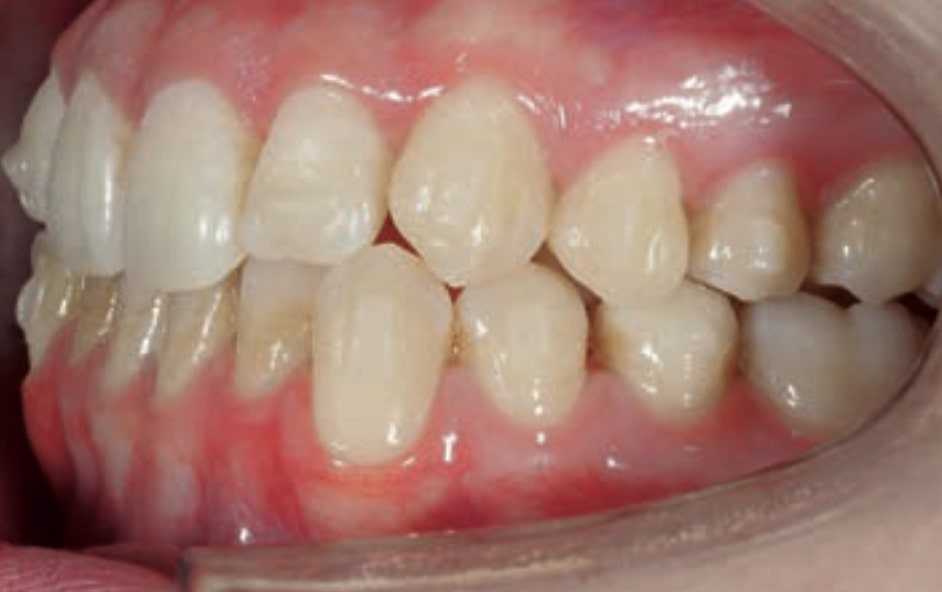

Chief complaint: The patient, a 19-year-old woman, was evaluated to undergo orthodontic treatment using the Angel Aligner Pro system. She presents with a skeletal Class III, mesofacial, with a dental Class III malocclusion and a 2 mm deviation of the lower midline to the left. Teeth 33 and 43 are out of the arch and cortical bone, with a crossbite issue on tooth 33. Fortunately, no functional issues affecting swallowing or breathing have been detected. The patient’s motivation for starting treatment was a general review of her dental and aesthetic health. The soft tissue analysis reveals mandibular protrusion that influences her facial profile. This diagnosis highlights the need for a comprehensive approach to address dental and skeletal misalignments, improving both the patient’s functionality and facial aesthetics.

• Dental Class III, 2 mm deviation of the lower midline to the left. 33 and 43 out of the arch and the cortical bone.

• Crossbite of 33.

• Solve the Crossbite of Tooth 33: Correct the position of tooth 33 to eliminate the crossbite, contributing to a more balanced occlusion.